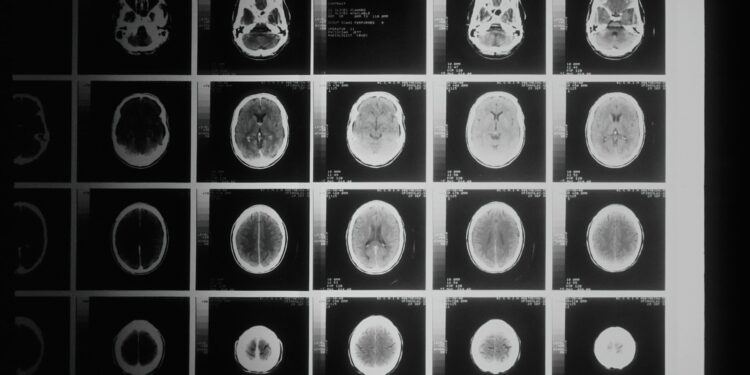

Researchers from the Buck Institute for Research on Aging in Novato, CA, have delved into the impact of calorie restriction on protecting the brain from aging. Their findings, recently published in the journal Nature Communications, pinpoint a specific gene that undergoes enhancement through calorie restriction, facilitating processes crucial for healthy brain aging. Dr. Lisa Ellerby, a professor at the Buck Institute for Research on Aging and co-senior author of the study, highlighted the significance of studying calorie restriction’s effects on brain aging, given the vulnerability of the brain during the aging process.

The decision to explore the relationship between calorie restriction and brain aging stems from the recognition of dietary restriction as a significant intervention in the aging process. Dr. Ellerby emphasized that the brain is particularly susceptible to the aging process, making it crucial to understand factors modulated by dietary restriction that can protect the brain. The study serves as an initial step in comprehending how various forms of caloric restriction, including intermittent fasting, may impact brain aging.

In line with this research, a review published in February 2021 suggested that dietary restriction could potentially safeguard the brain against neuroinflammation and neurodegeneration. Dr. Ellerby stressed that age-related diseases pose a significant challenge in the 21st century, with aging being the primary risk factor for various brain diseases. She highlighted the importance of exploring ways to postpone or slow down the aging process, as there are currently no available treatments to cure diseases like Alzheimer’s and Parkinson’s. Understanding methods to prevent or decelerate the progression of neurodegenerative diseases becomes crucial in addressing these challenging health issues.